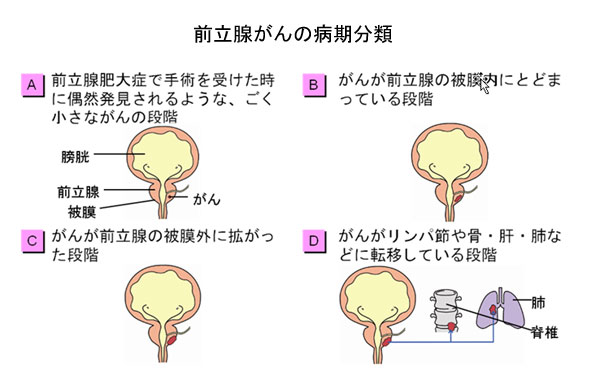

前立腺がんの特徴 がんのつらさ 痛みや症状をつたえて シオノギ製薬 塩野義製薬

がん情報サイト がん情報各論 患者さん向け

がん電話相談から 前立腺がんグレーゾーン 次の検査は 産経ニュース

前立腺がん 診療内容 泌尿器科 独立行政法人国立病院機構 京都医療センター

平塚市の泌尿器科 かなめ泌尿器科内科クリニック 前立腺がん検診ついて

平塚市の泌尿器科 かなめ泌尿器科内科クリニック 前立腺がん検診ついて